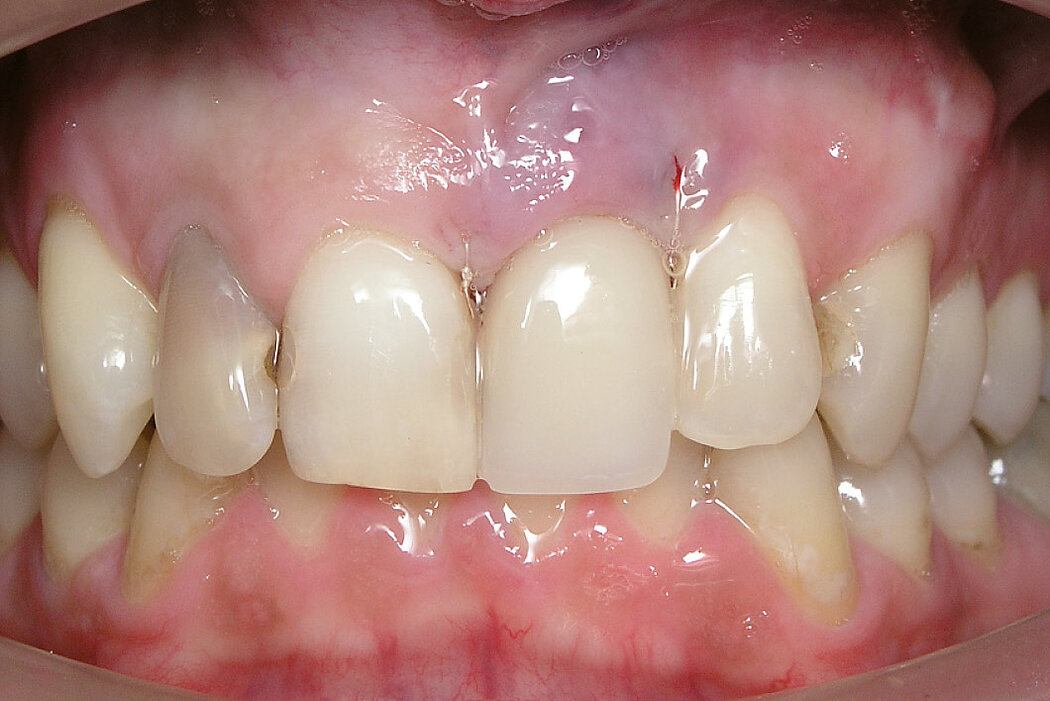

Ridge Preservation in socket with preserved buccal bone wall

Clinical challenge

Soft and hard tissues are well preserved without any scarring on the buccal or occlusal aspect.

Aim / Approach

Delayed implant placement 4 months after extraction. Minimally invasive treatment of the socket.

Conclusion

Good/mature/solid bone obtained 4 months after treatment. Fast and scar-free soft tissue regeneration. Optimal clinical and esthetic result for the patient.